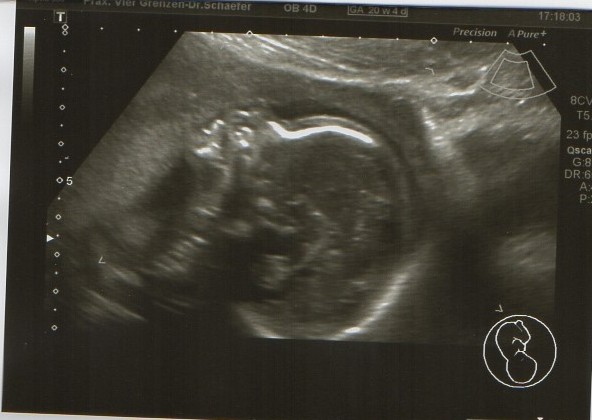

Heute gab es ein Fotoshooting der besonderen Art beim Opa auf Arbeit. Sein Kollege, der stellvertretende Chefarzt der Kinderklinik und gleichzeitig Guru des Ultraschalls, hatte sich bereit erklärt den werdenden Eltern noch ein paar aktuelle Fotos zu machen. Leider gab es kein 3D, aber dafür ein paar süße Fotos und vor allem Videos unseres Sohnemannes, der sich die ganze Zeit über ruhig verhielt und sich der Kamera, äh dem Schallkopf stellte.